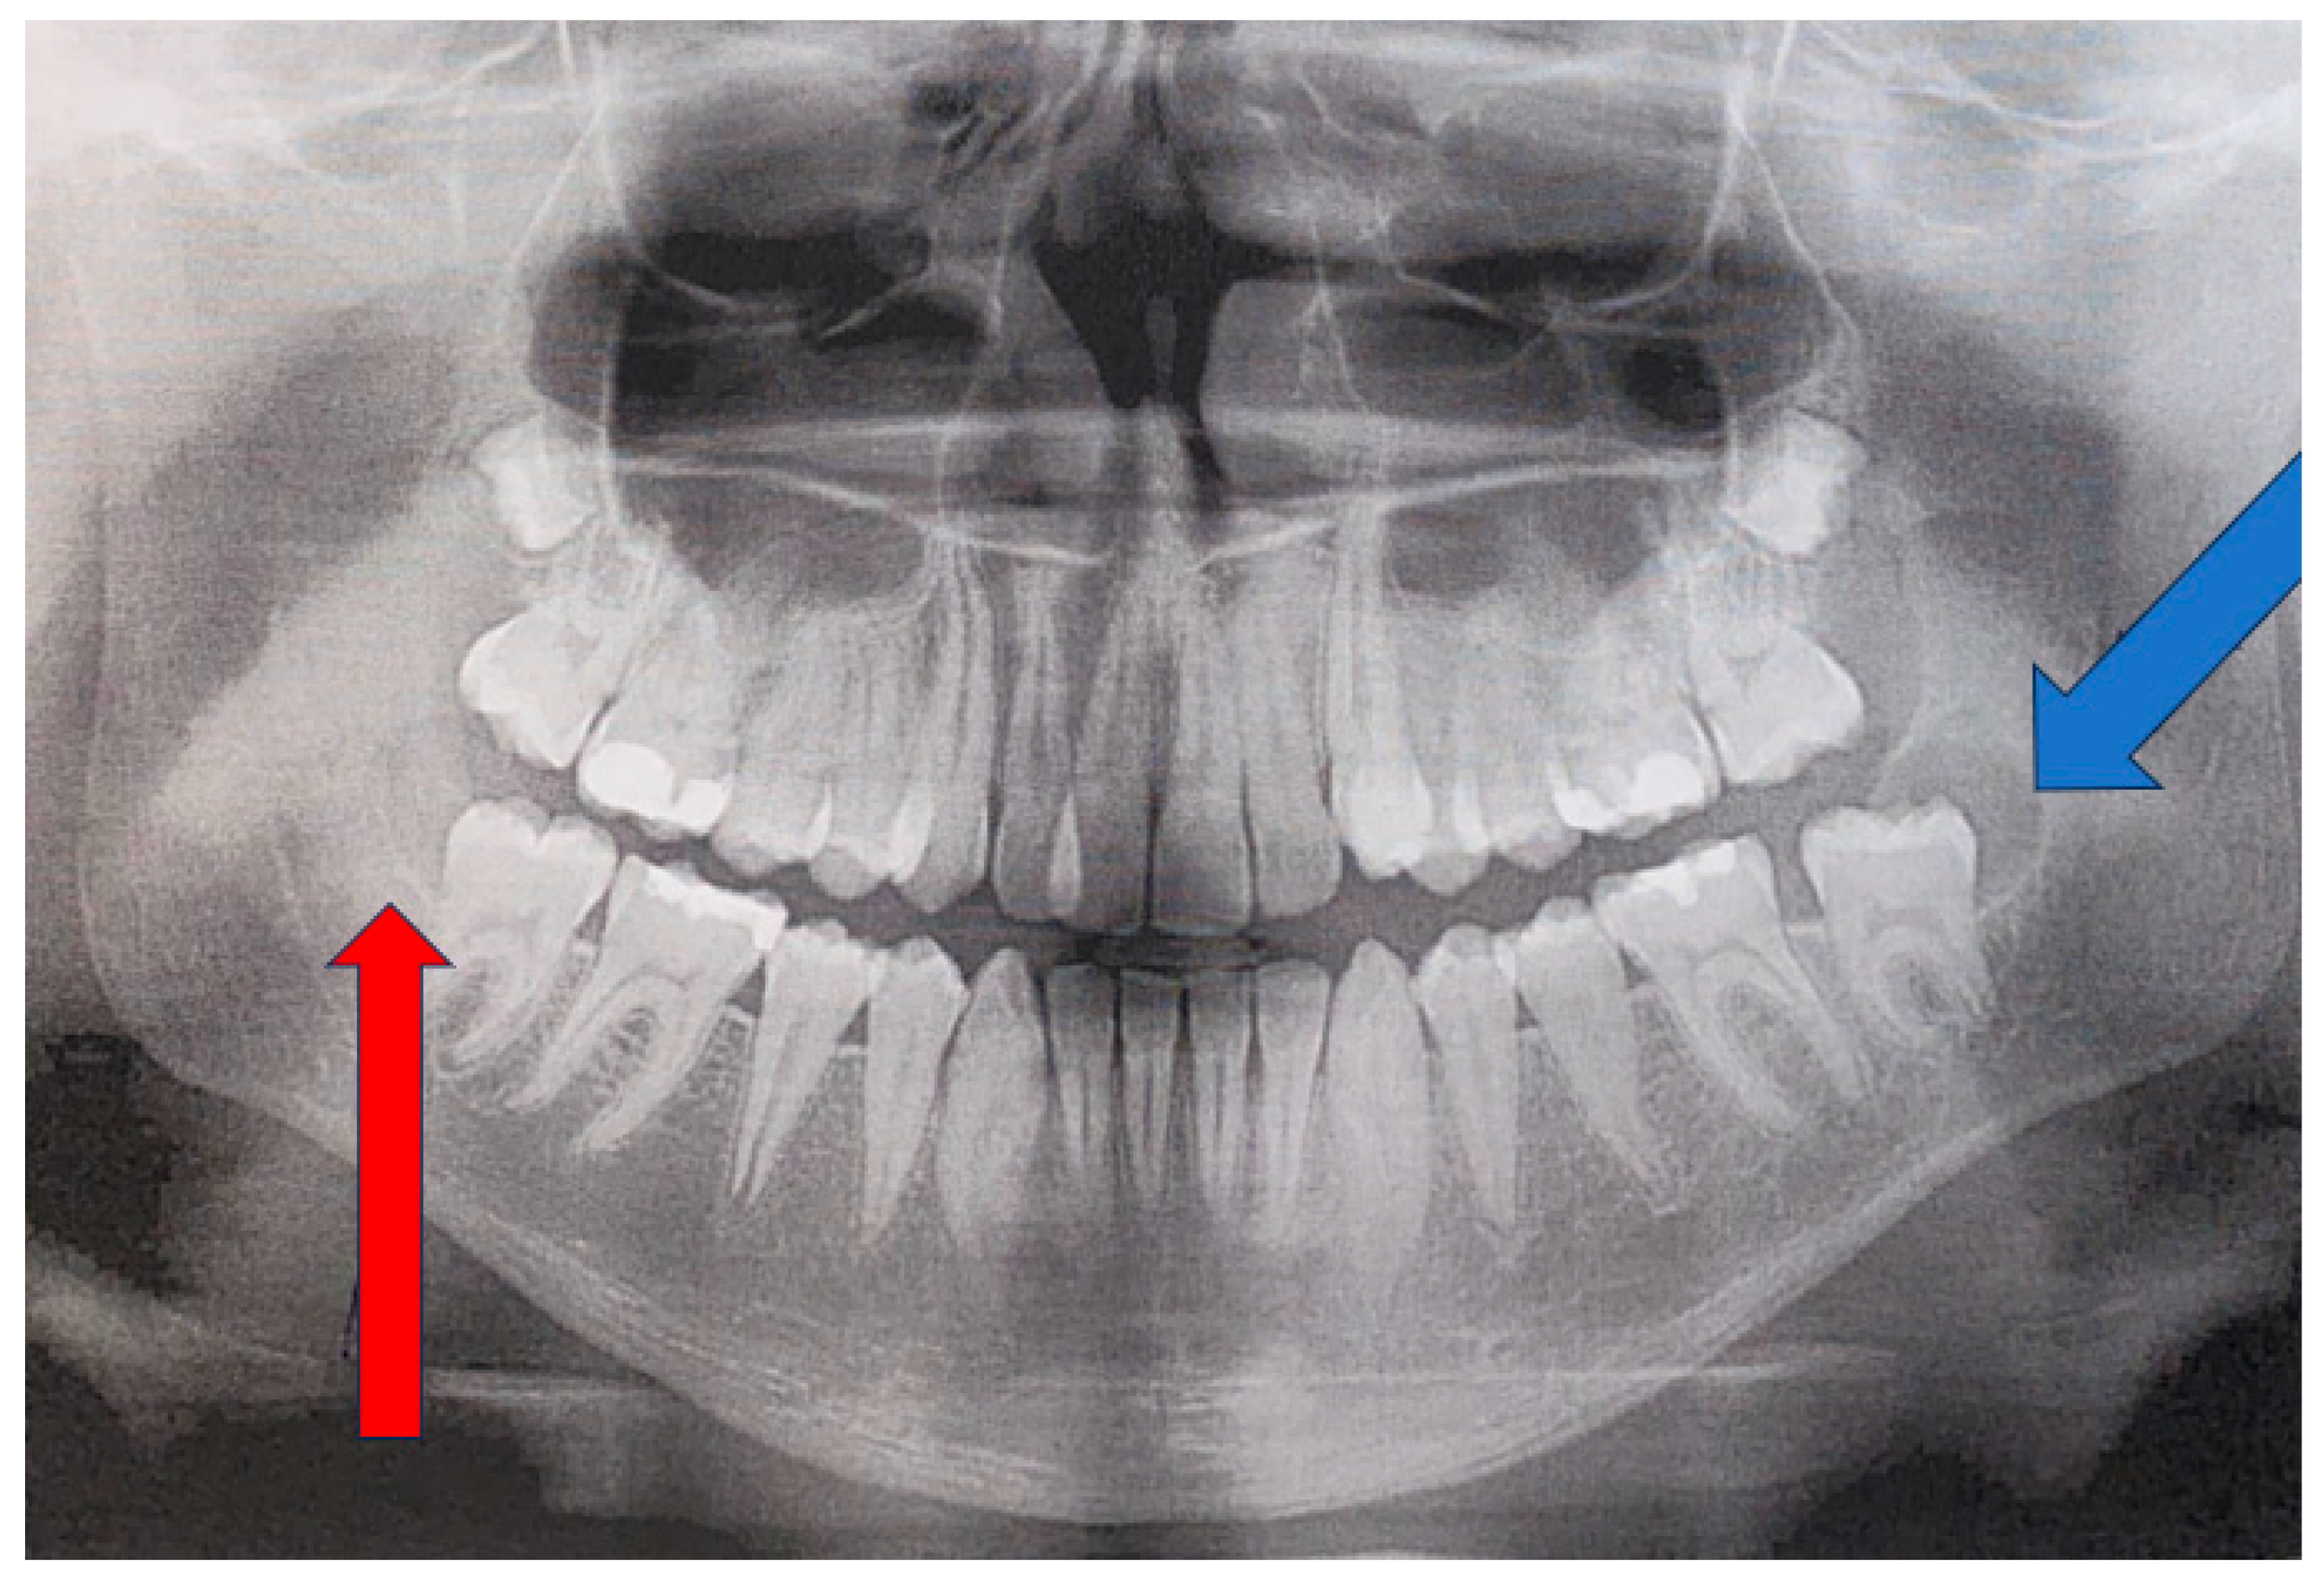

Control OPG radiograph after 18 months revealed the formation of a cystic lesion of radiolucent and unilocular appearance in the left retromolar area of the mandible (blue arrow). On the other hand, the right retromolar area was free of any disease, with normal bone contour and shape (red arrow). Because a left retromolar lesion was associated with a freshly, not fully yet erupted left mandibular second molar, an assumption of a follicular cyst (FC) was made. Since the lesion was unilocular and radiolucent, without any calcified or mineralized structures inside, a comparison with a cyst was made. In this case, the OPG showed no septations, ridges, or calcifications within the unilocular lesion (Figure 3). As the lesion progressed over time in the absence of clear clinical symptoms, CBCT imaging was performed to improve diagnostic assessment. If any suspicious findings, such as bone erosion, extracortical spread, resorption of adjacent teeth/roots, cortical bone erosion or swelling with a periosteal reaction, loss of bone structure with irregular borders, or other worrisome symptoms, are found on CBCT, a decision to perform either a biopsy or excisional biopsy should be made. The choice of approach depends on the lesion’s shape, size, and anatomical location within the jaw. The patient exhibited no worrisome swelling intraorally; their teeth were stable without any mobility, and bone asymmetry was not noted. In the following case, a needle biopsy did not reveal any fluid accumulation typical of a classic cyst of odontogenic origins.

Figure 3. An OPG 18 months later with a visible, clearly defined radiolucent unilocular area behind the second left molar (blue arrow).